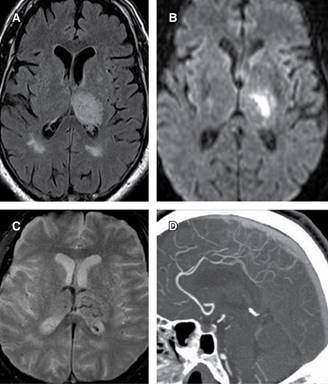

Inicia padecimiento actual siete días previos a su ingreso con cefalea occipital de intensidad moderada, que se intensifica al paso de los días, haciendo énfasis en que empeoraba al estar acostada, se agregan náuseas y vómitos, sugestivos de cráneo hipertensivo, por lo que acude a hospital, donde ingresa con Glasgow de 15 puntos, se realiza RM, que muestra trombosis del seno venoso transverso izquierdo y hemorragia intraparenquimatosa temporoparietal izquierda (Figura 1). La paciente presenta deterioro del estado neurológico, requiriendo manejo avanzado de vía aérea y es trasladada a Unidad de Cuidados Intensivos.

Figura 1: A) En plano transversal en secuencia fast-FLAIR se observa hiperintensidad en tálamo izquierdo. B) Venografía por RM en corte transversal se observa la trombosis del seno transversal izquierdo a nivel de tálamo izquierdo. C) En secuencia T2 no se delimita de manera objetiva la afección venosa. D) Venografía por RM en corte sagital revela imagen isointensa en seno sagital superior.